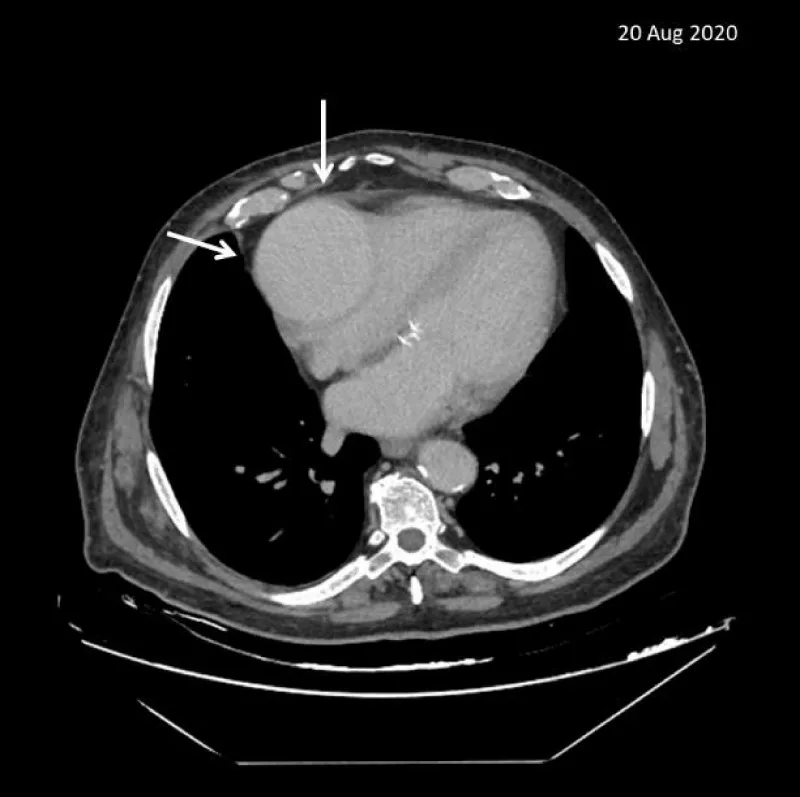

He underwent an abdominal baseline CT scan and no pathological findings were reported. Accidentally at the thoracic level, it was reported a suspected pericardial cyst (75 x 80 mm), with partial compression of the right chambers (Figure 1).

Figure 1: Abdominal/chest baseline CT scan shows a suspected pericardial cyst with partial compression of the right chambers.